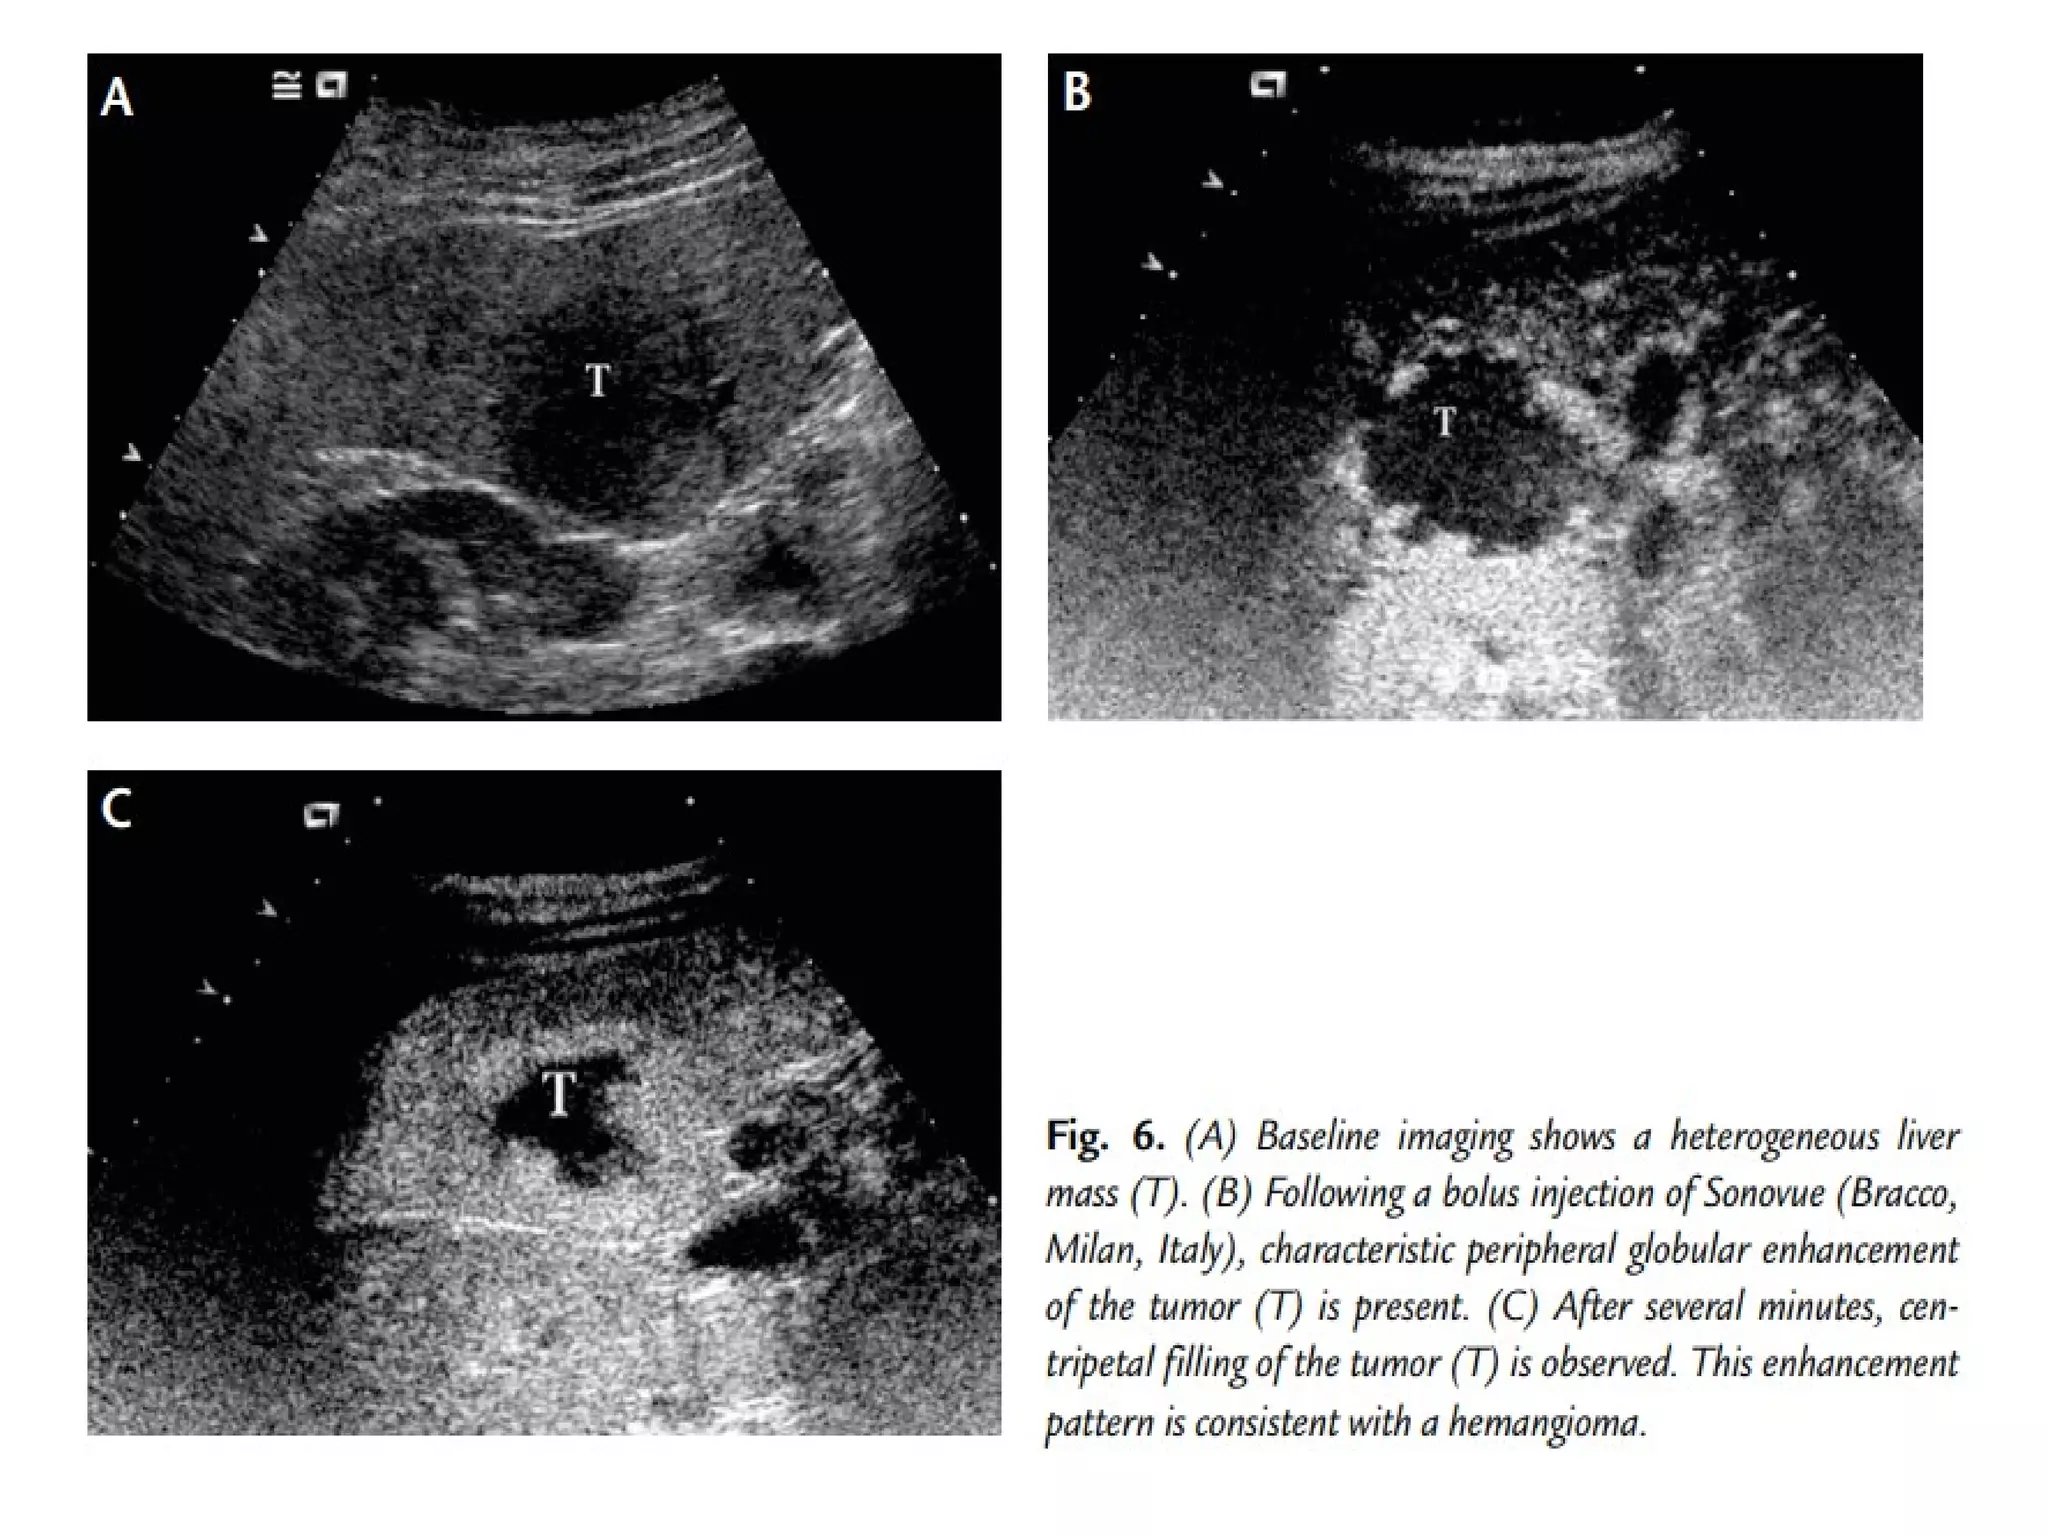

CONTRAST-ENHANCED

ULTRASONOGRAPHY

• US contrast media consists of air or other

gases which act as echo enhancers

• Contrary to other contrast media which get

distributed to extravascular space,

microbubbles remain confined to the vascular

system ( blood pool agents).

• Microbubbles may produce upto 25 db- more

than 300 fold increase in echo strength.

PRINCIPLES

• BACKSCATERRING: At very low acoustic power

( MI <0.1) the bubbles act as simple but powerful echo

enhancers. This regimen is most useful for spectral

Doppler enhancement but is rarely used in the abdominal

organs.

• BUBBLE RESONANCE AND HARMONICS: At slightly higher

intensities (0.1 <MI > 0.5) the bubbles emit harmonics as

they undergo nonlinear oscillation. These nonlinear echoes

can be detected by contrast-specific imaging modes. Pulse

inversion imaging is an example of such a method.

BUBBLE RUPTURE: At high acoustic power ( MI>

0.5) bubbles can be disrupted deliberately,

creating a strong, transient echo. Detecting

this echo is one of the most sensitive means

available to image bubbles in very low

concentration